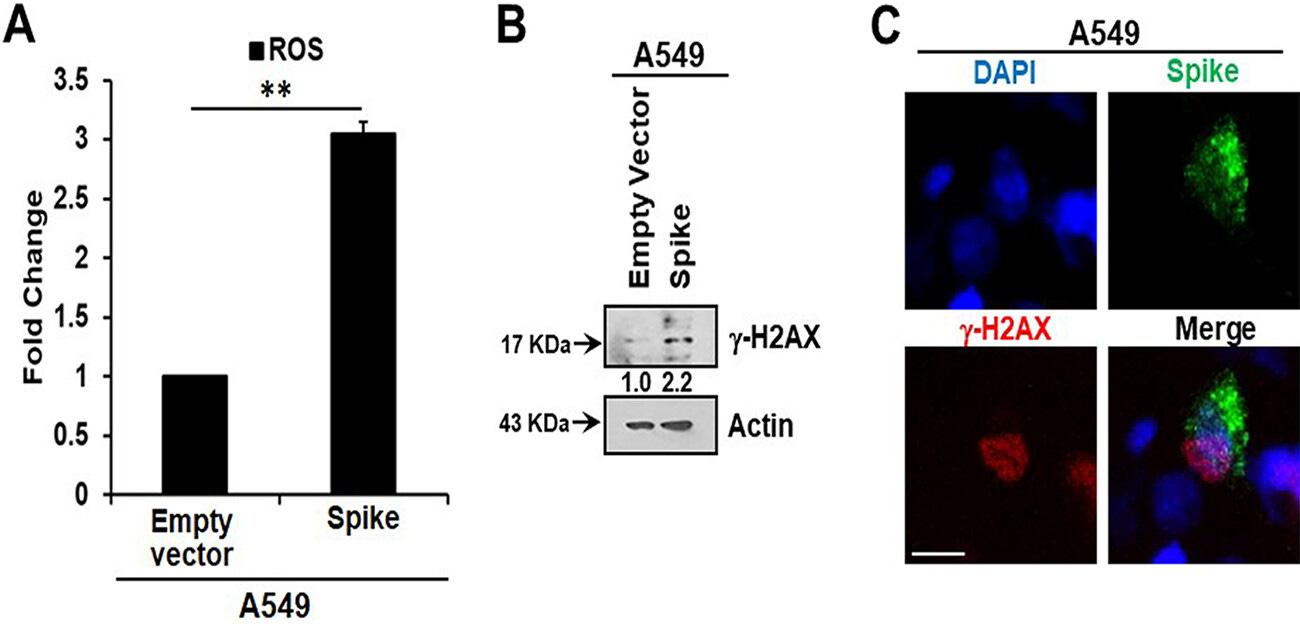

Inhibition of IL-6 trans signaling by tocilizumab and inhibition of inflammatory receptor signaling by the Bruton’s tyrosine kinase (BTK) inhibitor zanubrutinib, prior to exposure of CM to endothelial cells, inhibited p21 and p16 induction. We also observed an increase in reactive oxygen species (ROS) in A549 spike-transfected and endothelial cells exposed to spike-transfected CM. ROS generation in endothelial cell lines was reduced after treatment with tocilizumab and zanubrutinib.

Here, we measured intracellular ROS and observed an approximately 3-fold increase in ROS in A549 spike-transfected cells compared to levels in empty plasmid-transfected control cells (Fig. 2A). Increased production of intracellular ROS contributes to DNA damage, leading to cellular senescence. We observed an increase in the DNA damage response marker γ-H2AX in cells transfected with the viral spike gene (Fig. 2B). γ-H2AX was found to be localized to the nucleus in viral spike-transfected A549 cells (Fig. 2C). Our results indicated that SARS-CoV-2 spike protein expression induces a senescent state in spike-transfected A549 cells that is associated with the DNA damage response and increased ROS generation.